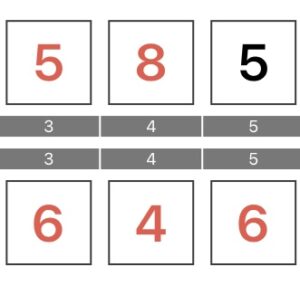

歯周ポケット検査についてですが、

健康な歯ぐきでは歯との間の溝(歯周ポケット)が2~3mm程度ですが、

歯周病になるとこの溝が深くなっていき、数値が上昇します。

つまり、歯周ポケットの数値が高い=歯周病が進行している

ということになります。

この数値が最初のレントゲン写真時の歯周ポケットの数値です。

2~3mmが健常ですから、この数値は良くないことがわかります。

歯周ポケット検査の数値も改善がみられました。